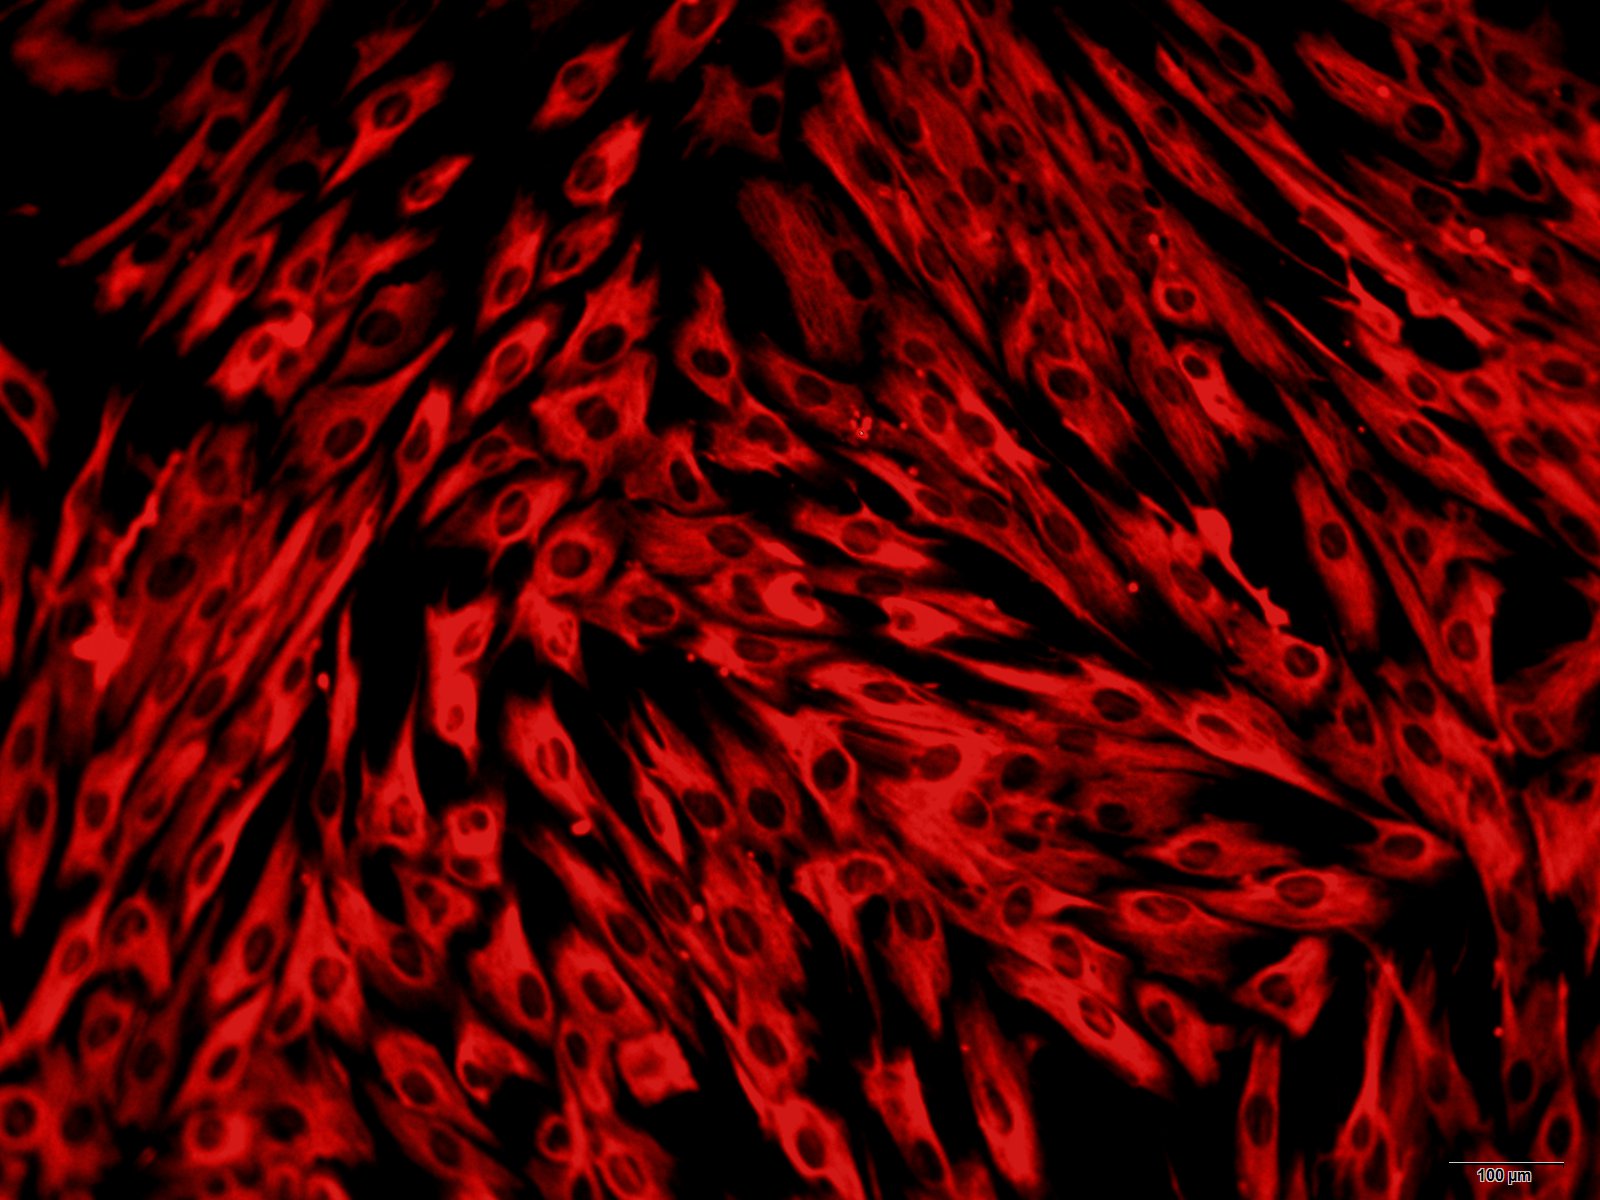

结肠分升结肠、横结肠、降结肠和乙状结肠4部分,大部分固定于腹后壁,结肠的排列酷似英文字母“M”,将小肠包围在内。结肠横切面由内到外依次为:黏膜(上皮层、固有层、黏膜肌层),黏膜下层(疏松结缔组织),肌层(内环形、外纵行两层平滑肌),外膜(纤维膜或浆膜)。肠黏膜上皮细胞是机体内外环境的重要屏障,持续暴露于大量抗原中,也是机体面对病原微生物的第一道防线。因此,肠黏膜上皮细胞除有吸收、分泌和转运等重要生理功能之外,在黏膜先天性和获得性免疫防御机制中也起着重要作用。肠黏膜上皮细胞作为首先接触抗原的细胞,在黏膜免疫反应的起始阶段发挥关键作用,它决定黏膜免疫反应的发生、性质和强度。探讨正常结肠黏膜上皮细胞的分离、体外培养方法,为研究肠黏膜上皮细胞以及与肠黏膜相关疾病建立合适的细胞模型。

本公司生产的小鼠结肠上皮细胞采用酶解法制备而来,细胞总量约为5×105/T25方瓶,CK-18、CK-19呈阳性,细胞纯度可达90%以上,且不含有HIV-1、 HBV、HCV、支原体、细菌、酵母和真菌等。